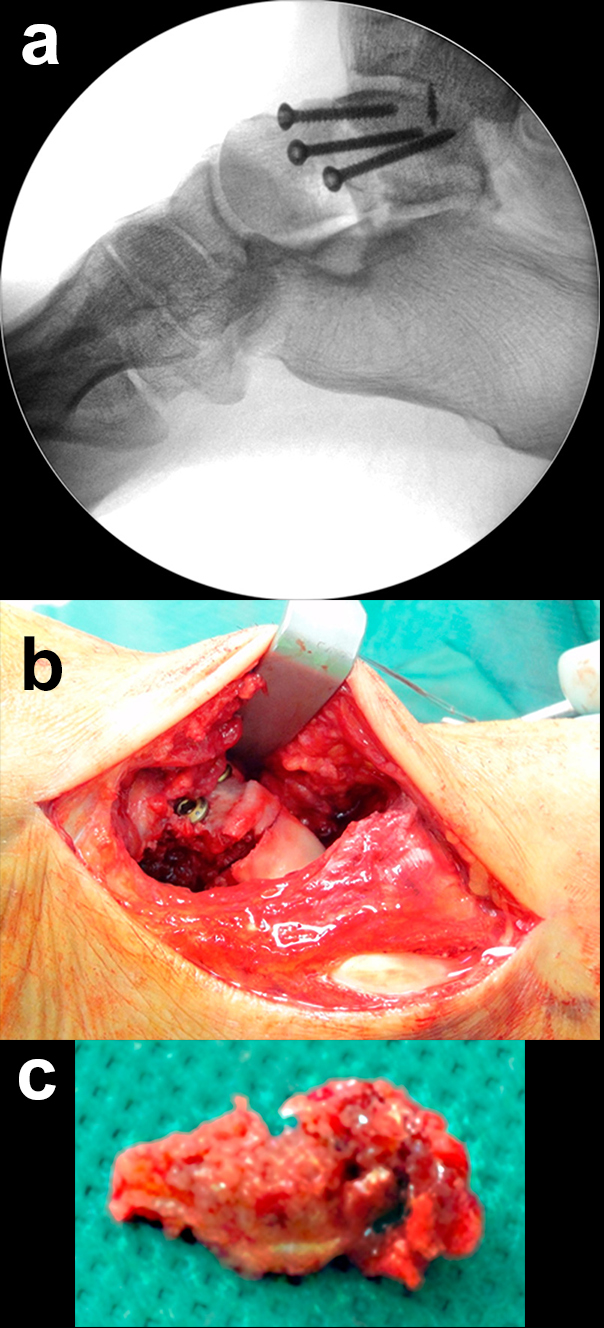

Talushalsfrakturen

Dislozierte Talushalsfrakturen werden zur anatomischen Reposition über einen anteromedialen und über einen zusätzlichen anterolateralen Zugang adressiert 244. Durch die bilaterale Kontrolle der Reposition können Rotations- oder Achsenfehlstellungen des Talus verhindert werden. Der anteromediale Zugang wird geschwungen vom Vorderrand des Innenknöchels bis zur Tuberositas ossis navicularis ausgeführt (Abb. 5). Der anterolaterale Zugang liegt zwischen Fibulaspitze und Proc. anterior calcanei. Im eigenen Vorgehen wird ein schräg verlaufender Zugang nach Ducroquet-Ollier vor dem Außenknöchel und entlang der natürlichen Hautfältelung bevorzugt 4 (Zwipp, Rammelt 2014). Der Zugang zum Proc. fibularis tali und lateralen Talushals erfolgt direkt über den Sinus tarsi.

Die Reposition des Talushalses erfolgt unter wechselseitiger Sicht von medial und lateral 24. Zur Manipulation können senkrecht zur Fraktur in die Hauptfragmente eingebrachte Kirschnerdrähte hilfreich sein 4. Nach temporärer Retention mit axial eingebrachten Kirschnerdrähten und visueller sowie Bildwandlerkontrolle werden zur Stabilisierung vorzugsweise Schrauben benutzt (Abb. 6). Müssen diese nahe zum Talonavicular-Gelenk eingebracht werden, sind Doppelgewindeschrauben oder die Verwendung einer Kopfraumfräse zum Versenken des Schraubenkopfes unter Knorpelniveau erforderlich. In jedem Fall sollte bei der Schraubenosteosynthese aufgrund der typischerweise vorliegenden medialen Trümmerzonen auf die Vermeidung von Zugkräften geachtet werden, um eine Verkürzung der medialen Seite des Talus mit nachfolgender Varusfehlstellung zu vermeiden 30. Kleinste, nicht refixierbare Fragmente werden verworfen, um freien Gelenkkörpern vorzubeugen. Auf der lateralen Seite hingegen liegt recht häufig eine einfache Fraktur vor, welche in einem Kortikalis-Sporn am Proc. fibularis tali ausläuft und sich für eine Zugschraubenosteosynthese eignet. Die Verwendung kanülierter Schrauben kann im Einzelfall hilfreich sein. Es ist jedoch darauf zu achten, dass es nach dem Überbohren des Führungsdrahtes nicht zu einer erneuten Dislokation der Fragmente kommt 24.